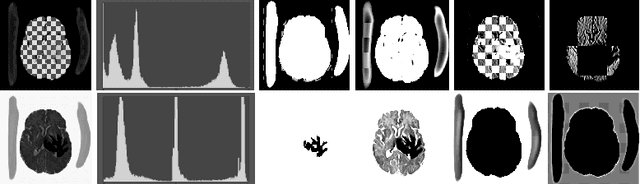

Abstract:Brain extraction is a fundamental step for most brain imaging studies. In this paper, we investigate the problem of skull stripping and propose complementary segmentation networks (CompNets) to accurately extract the brain from T1-weighted MRI scans, for both normal and pathological brain images. The proposed networks are designed in the framework of encoder-decoder networks and have two pathways to learn features from both the brain tissue and its complementary part located outside of the brain. The complementary pathway extracts the features in the non-brain region and leads to a robust solution to brain extraction from MRIs with pathologies, which do not exist in our training dataset. We demonstrate the effectiveness of our networks by evaluating them on the OASIS dataset, resulting in the state of the art performance under the two-fold cross-validation setting. Moreover, the robustness of our networks is verified by testing on images with introduced pathologies and by showing its invariance to unseen brain pathologies. In addition, our complementary network design is general and can be extended to address other image segmentation problems with better generalization.